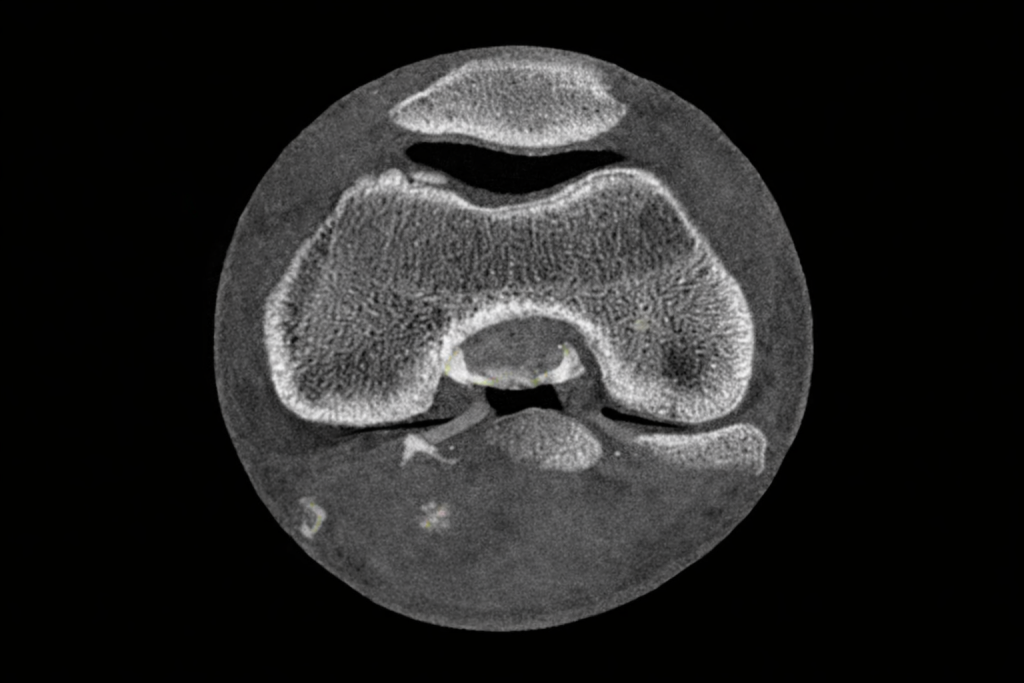

CT検査は、体の中を輪切りの画像で詳しく見る検査です。

輪切りで撮ったものを立体の形にする検査です。

さらにレントゲンやCTが「影をそのまま写し出す」のに対し、MRIは「信号をデジタル画像化」する検査になります。